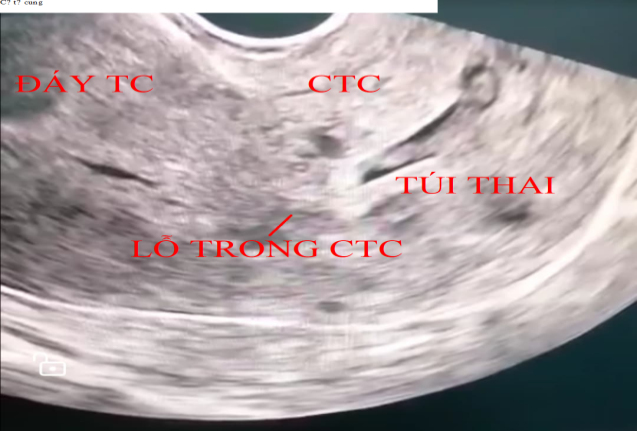

Hình 1. Hình ảnh siêu âm đầu dò âm đạo túi thai làm tổ tại cổ tử cung; cổ tử cung phình to; dòng máu xung quanh nguyên bào nuôi thấy trên phổ Doppler

Triệu chứng phổ biến nhất là chảy máu âm đạo sau một thời gian vô kinh, thường không đau và đôi khi chảy máu ồ ạt. Tiêu chuẩn lâm sàng bao gồm [4]: Tử cung nhỏ, cổ tử cung phình to; Lỗ trong cổ tử cung kín; Nạo niêm mạc tử cung không có mô nhau; Lỗ ngoài cổ tử cung mở to hơn sẩy thai.Mang thai OCTC sớm cũng có thể không có triệu chứng và được phát hiện tình cờ trên siêu âm.Siêu âm qua ngã âm đạo có thể được thực hiện một cách an toàn ở những bệnh nhân thai OCTC và việc chẩn đoán chủ yếu dựa vào kết quả siêu âm. Theo Ushakov và cộng sự, người đã xem xét 117 trường hợp thai OCTC, siêu âm cải thiện chẩn đoán trước điều trị lên đến 81,8%. Những phát hiện sau đây của siêu âm qua ngã âm đạo cho thấy có thai ở cổ tử cung [2]: Túi thai hoặc mô nhau thai được nhìn thấy trong cổ tử cung hoặc hoạt động của tim được ghi nhận dưới mức lỗ trong cổ tử cung với lỗ trong cổ tử cung đóng kín; Không có túi thai trong lòng tử cung; Hình dạng tử cung trở thành “đồng hồ cát” với cổ tử cung lớn.

Chẩn đoán phân biệt thai OCTC bao gồm các nguyên nhân khác của chảy máu sớm trong thai kỳ [5]: Sinh lý (chảy máu trong giai đoạn đầu thai kỳ); Mang thai ngoài tử cung ở các vị trí khác; Sẩy thai tự nhiên; Bệnh tế bào nuôi; Bệnh lý cổ tử cung, âm đạo hoặc tử cung; Tụ máu dưới màng đệm.Điều quan trọng là phải chẩn đoán phân biệt với thai trong tử cung đang sẩy nằm cổ tử cung, điều đó có thể được phân biệt bằng 'dấu hiệu trượt' trên siêu âm qua ngã âm đạo. Theo báo cáo của Jurkovic và cộng sự, khi đè dầu dò vừa phải lên cổ tử cung, túi thai sẩy trượt nhẹ khỏi kênh cổ tử cung, không giống như thai ở cổ tử cung [6]. Hơn thế nữa, dòng máu xung quanh nguyên bào nuôi có thể được thấy trên phổ Doppler trong trường hợp thai OCTC [7]. Nếu chẩn đoán không chắc chắn và bệnh nhân lâm sàng ổn định thì có thể đợi sau một ngày và siêu âm lại xem túi thai có di chuyển không. Bệnh nhân chúng tôi không xuất huyết tử cung, không có đau bụng, cổ tử cung lớn, sung huyết, tăng sinh mạch máu nhiều, lỗ ngoài tử cung hở, trên siêu âm thấy túi thai rõ với tim thai dương tính nằm dưới lỗ trong cổ tử cung và lỗ trong cổ tử cung đóng kín, thấy dòng máu xung quanh nguyên bào nuôi trên phổ Doppler, làm dấu hiệu trượt âm tính, sau 3 ngày thì bệnh siêu âm không thay đổi.